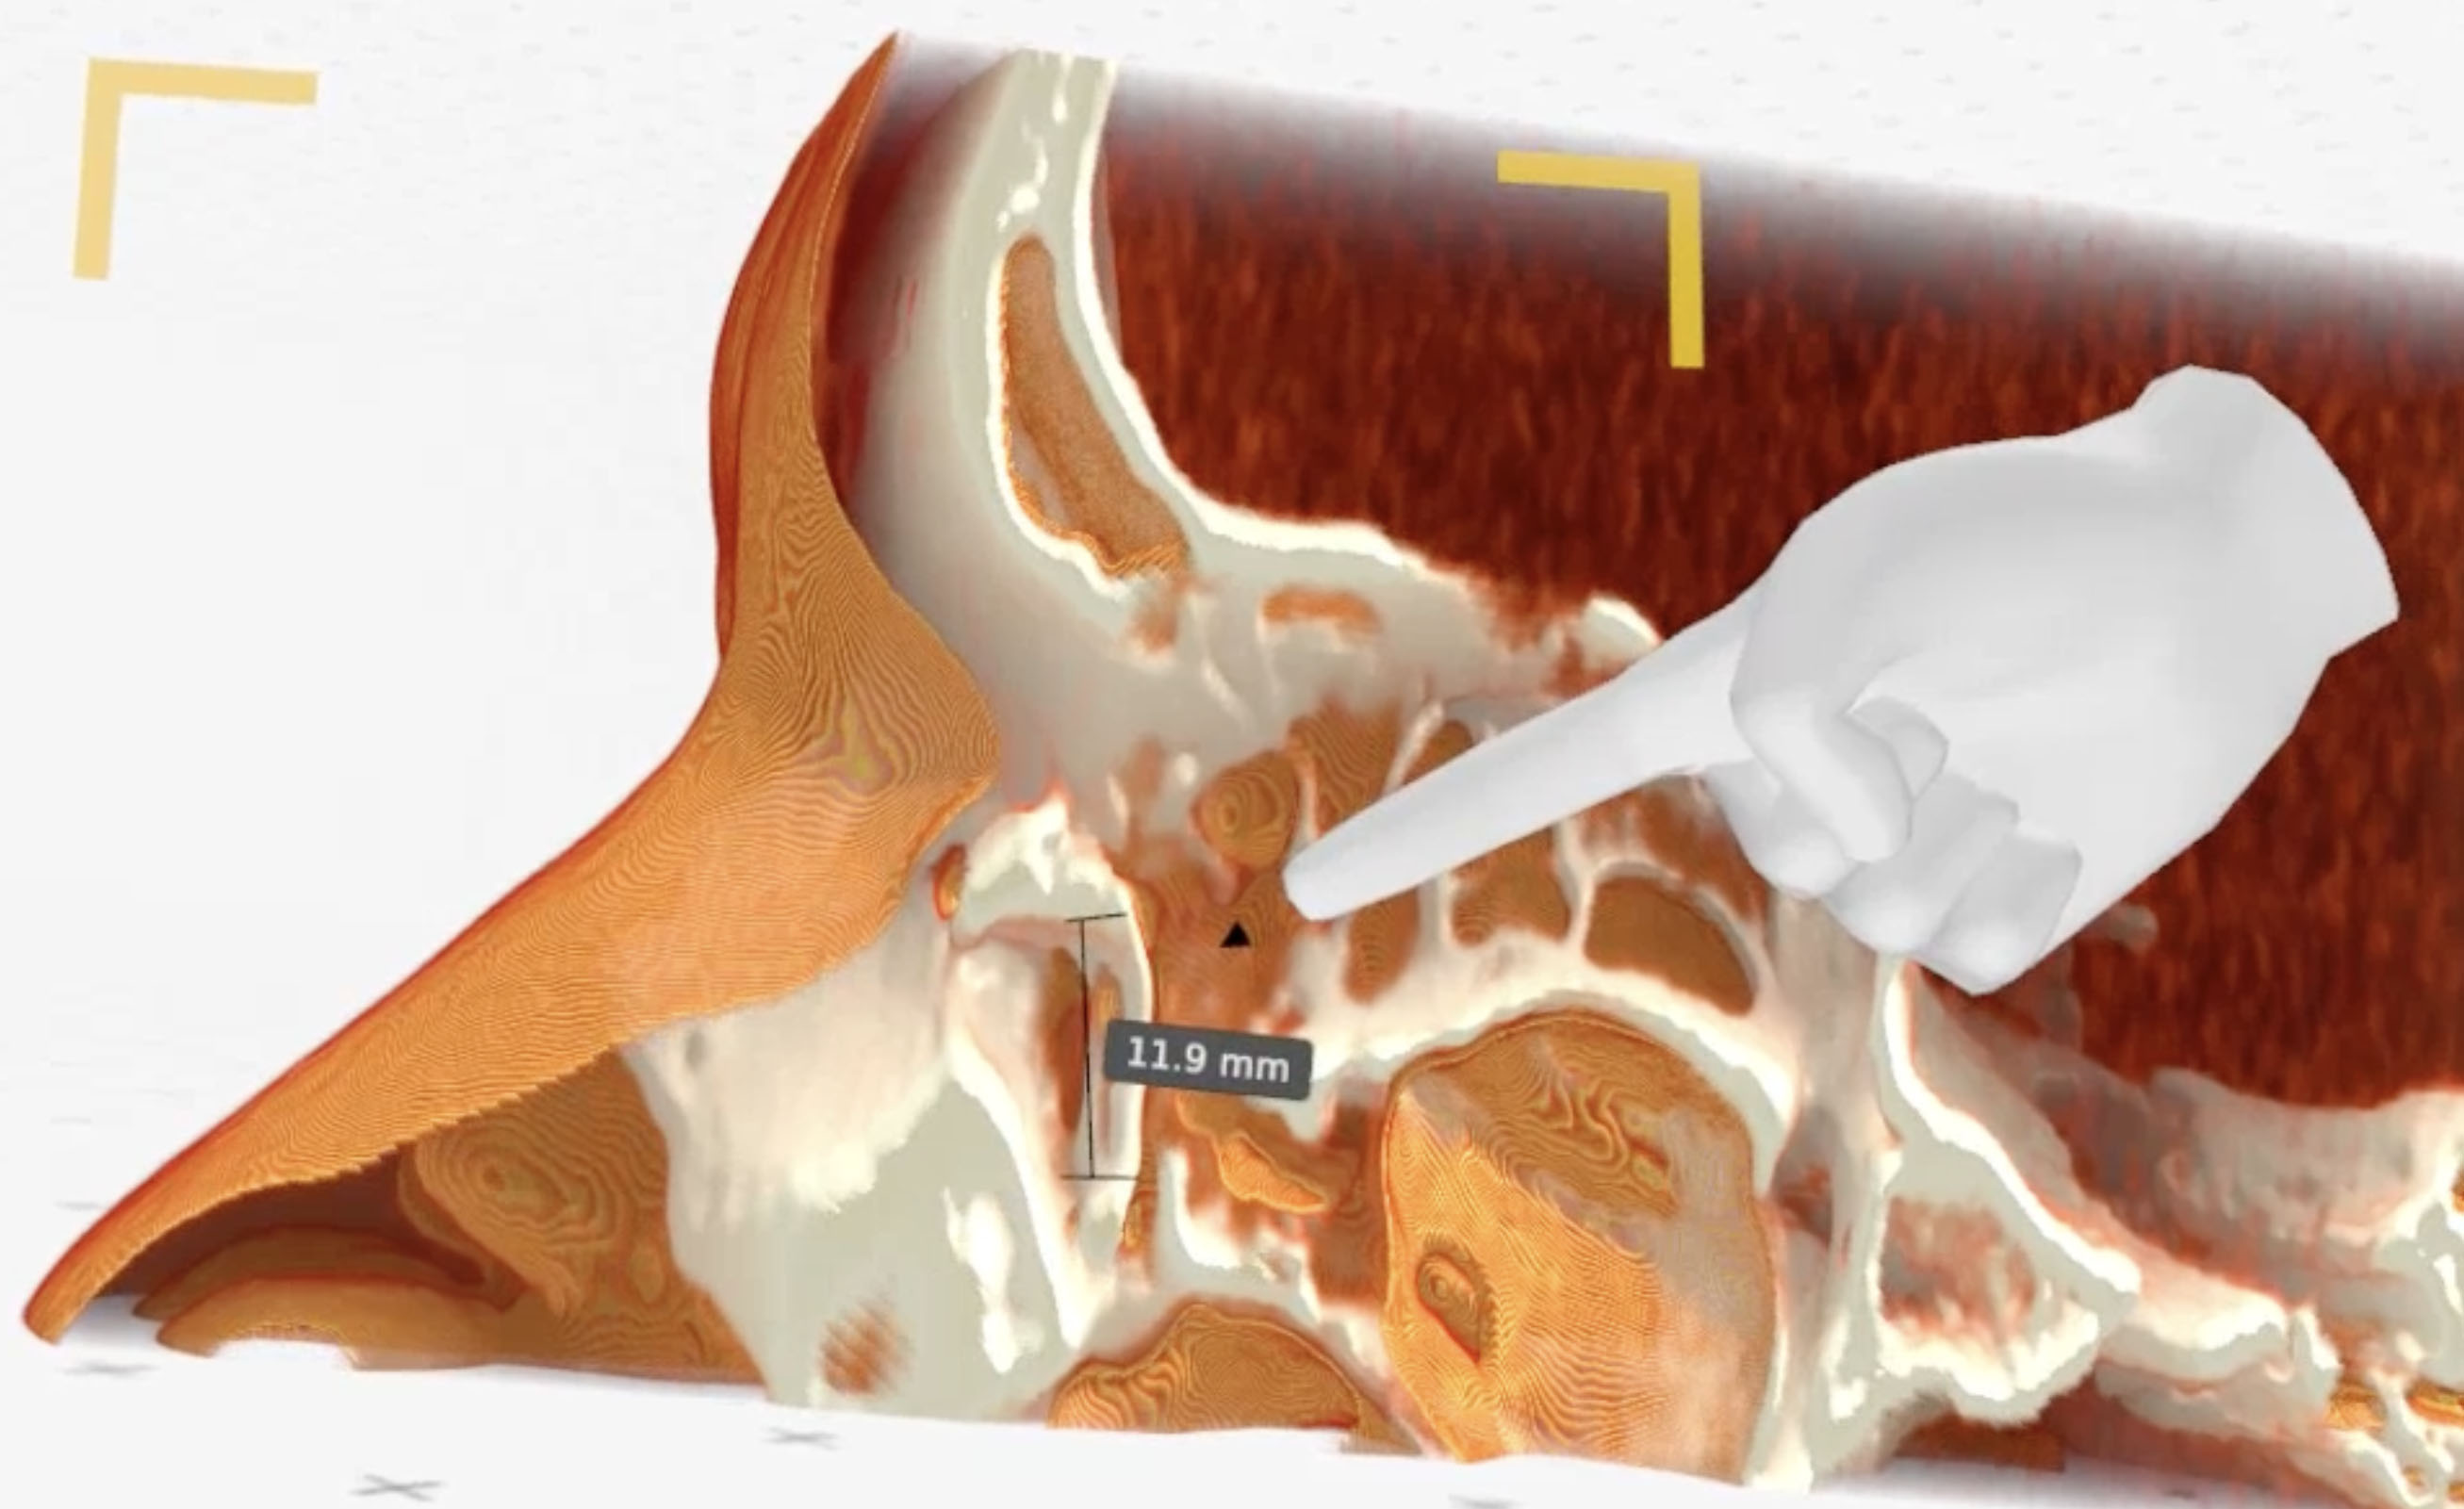

Medical Imaging XR (Medicalholodeck AG, Zurich, Switzerland) three-dimensional reconstructions obtained from CT-DCG DICOM files showed a well-defined lesion in the left lacrimal sac fossa, extending up to the beginning of the nasolacrimal canal (bony). The lacrimal sac appeared to be compressed against the posterior wall of the lacrimal fossa (Fig. 2-4).

Figure 4. Medical Imaging XR reconstruction shows vertical dimension of the cyst (11.9mm)